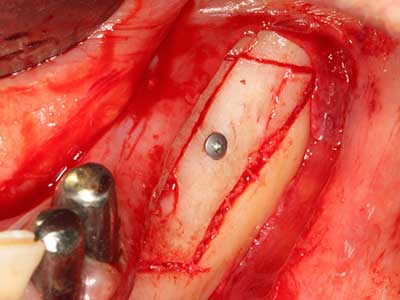

Fig. 17: Tomografía computarizada de un osteoma de crecimiento progresivo ...

Fig. 17b: justo al lado del canal alveolar con irritación nerviosa (vista lateral y coronal).

Fig. 18: Preparación de una tapa cortical con la sierra ósea piezoeléctrica (Piezomed, W&H).

Fig. 19: Zona operada después de neurolisis y eliminación del osteomo.

Fig. 20: La tapa ósea extraída se readapta y se fija mediante un tornillo para osteosíntesis (KLS Martin, Tuttlingen).